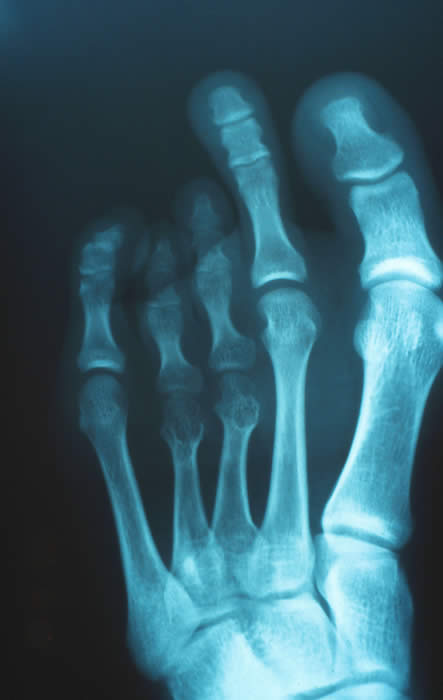

X線診断

一般に単純レントゲン像では、短縮趾に相当する中足骨の短縮が認められ、それによって中足趾節関節(MTP関節)が他趾にくらべて近位に位置しています。

右図では、第3,4趾の短縮がみられMTP関節が近位に位置しているため、母趾に28°の外反と第2趾にも軽度の外反を認めます。

第3、4中足骨の短縮はそれぞれ16mmと13mmでした。